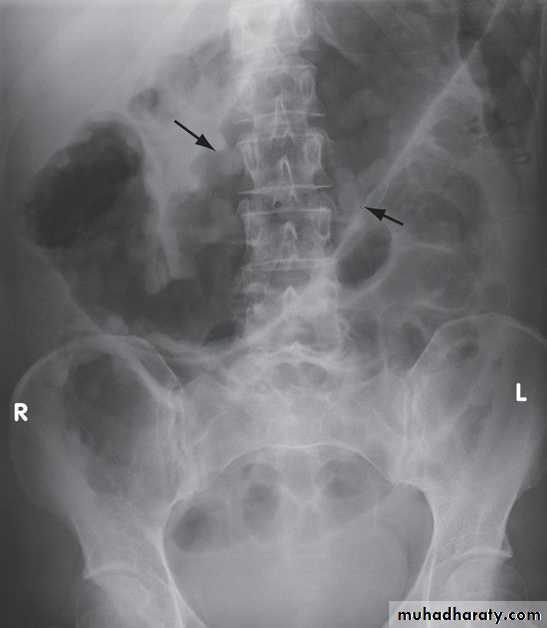

An abdominal X-ray should be taken daily because when the transverse colon is dilated to more than 6 cm there is a high risk of colonic perforation, although this complication can also occur in the absence of toxic megacolon.

Plain abdominal X-ray showing a grossly dilated colon due to severe ulcerative colitis. There is also marked mucosal oedema and 'thumb-printing' (arrows).